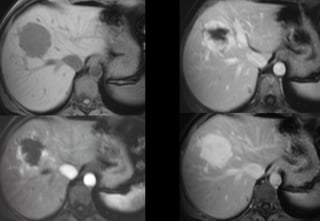

Hyperplasie Nodulaire Focale

T1 + có tiêm Gadolinium

• Thì sớm

–Tăng sinh mạch

–Sớm,

–Đồng nhất

Tăng sản thể nốt khu trú

• Thì muộn

– Ngấm thuốc sẹo xơ

– Không có vỏ

1- đồng nhất

2- tăng hoặc đồng tín hiệu trên T2

3- sẹo xơ tăng tín hiệu T2

4- ngấm thuốc sớm

5- sẹo xơ ngấm thuốc thì muộn

6- không có vỏ

Tiêu chuẩn HNF trên MRI

độ nhạy = 75%

độ đặc hiệu = 100%

HNF - IRM

đặc điểm

Mathieu et al. Gastroenterology 2000 Mar;118(3):560-4